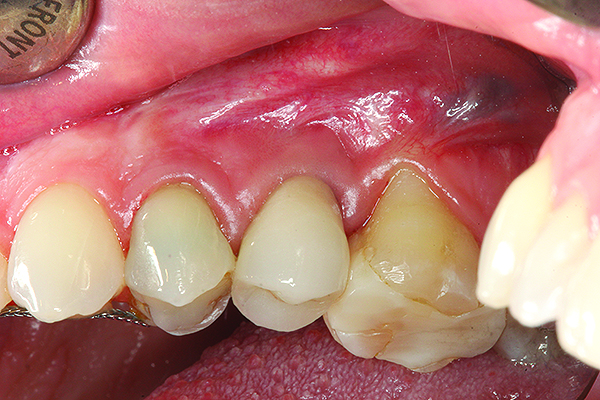

A implant restoration with a buccal dehiscence of bone and soft tissue caused by poor implant positioning, lack of keratinized tissue prior to implant placement, and soft tissue recession post implant restoration.

Figure 8

The implant of the patient shown in Figure 8 demonstrated all three of the red flag situations: it was placed too far buccally, had inadequate bone and soft tissue at the time of implant placement, and lost bone and soft tissue post implant placement. Correcting this required increased time, cost, and surgeries (Figure 9).

Prevention of this type of complication requires collaboration between the periodontist and the restorative dentist in the planning phase, and proper collaboration in the surgical placement, and in the restoration of the implants. No one member of the dental team can do it alone.